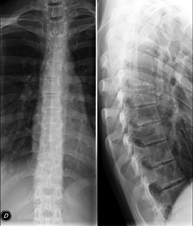

- Thoracic spine X-ray

This technique uses X-ray rendered imaging to examine the thoracic spine. Indicated for: trauma, back pain.

- Lumbar spine X-ray

This technique uses X-ray rendered imaging to examine the lumbar spine. Indicated for: sciatica, trauma, lower back pain.

- Spinal teleradiology

This technique uses X-ray rendered imaging to examine the entire spinal column, especially assessing the presence of scoliosis and pelvic dysmetria.